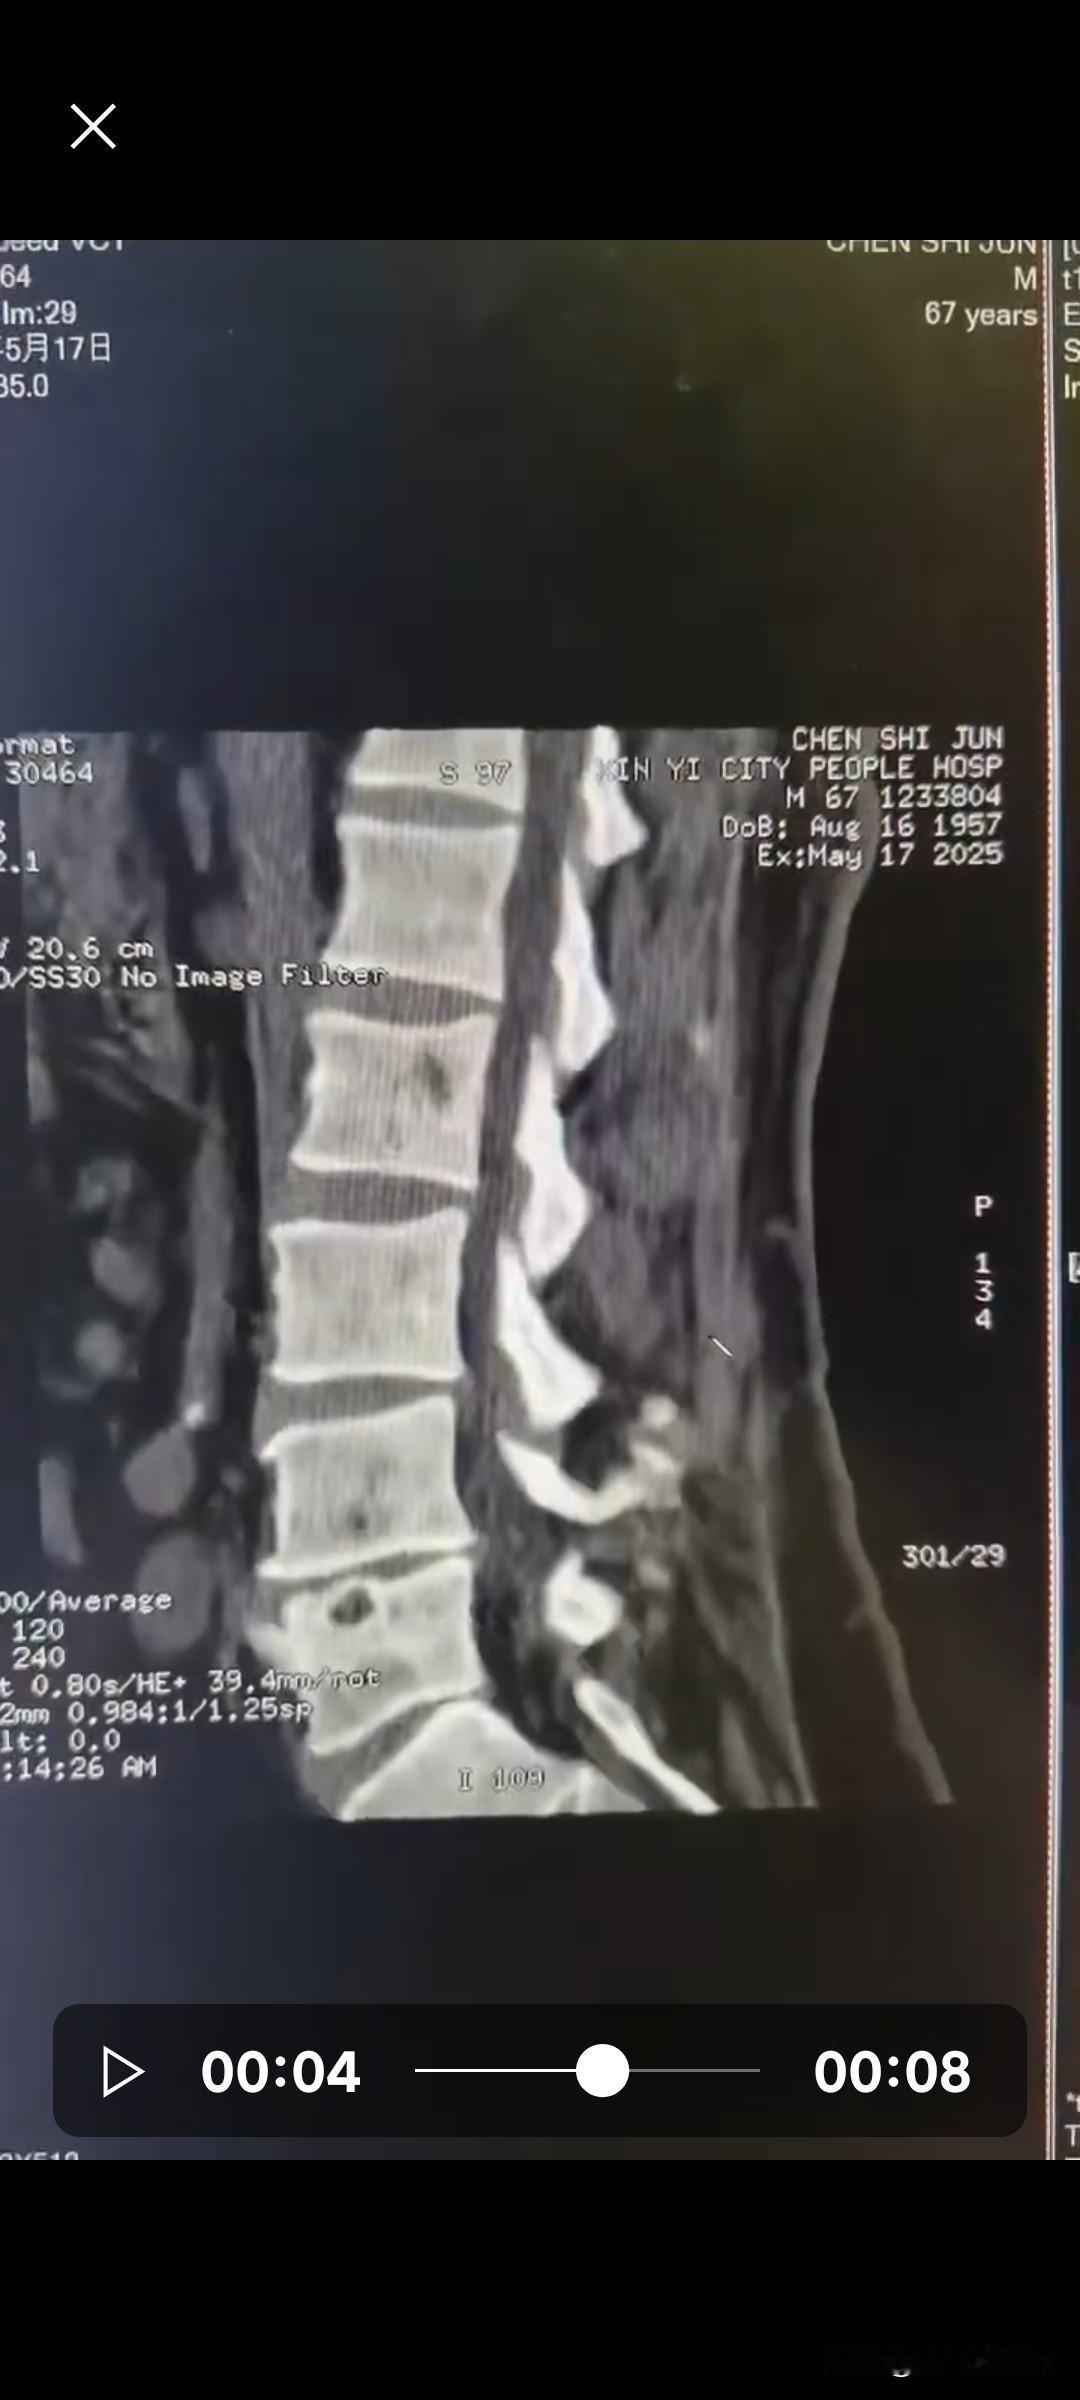

你可以把脊髓想象成一根从大脑通往下肢的电缆:上段(颈椎)是总干线,里面汇聚了去胳膊、去腿、去内脏的所有“电线”;中段(胸椎)是分干线,主要负责腿和肚子;下段(腰骶)是末端支线,主要管两条腿。位置越高,断掉的线路就越多。

颈椎段损伤(最上游)

这里是所有神经束汇集的地方。一旦受损,四肢全瘫(手和腿都不能动)。而且如果损伤在C3以上,膈神经中断,呼吸肌瘫痪,必须依赖呼吸机;如果伤在C3以下,还能靠膈肌呼吸,但四肢依然严重瘫痪。差一个节段,结局就差一个世界。